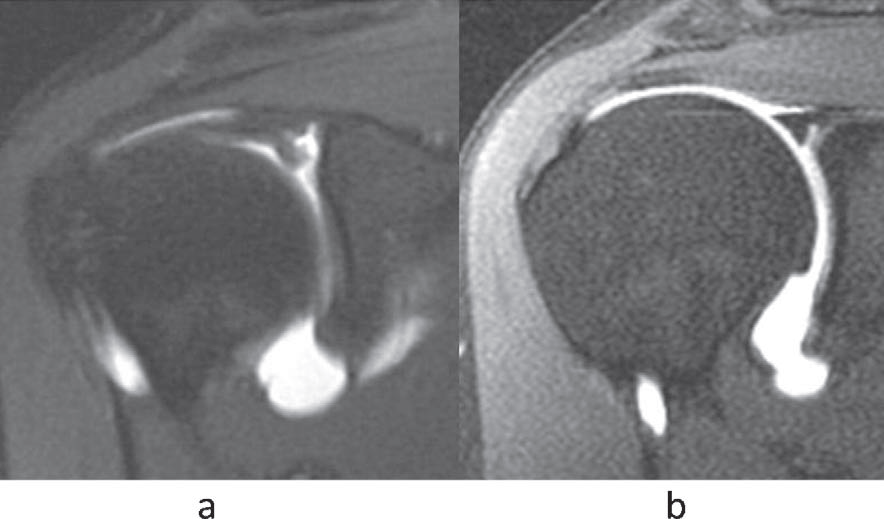

After appropriate clinical assessment, an MR arthrogram will be advised. A dye is injected into the shoulder and a magnetic field is used to create cross sectional images of the shoulder. The MRI scan will also diagnose other associated injuries (see picture below).

MR Arthrogram showing SLAP tear.